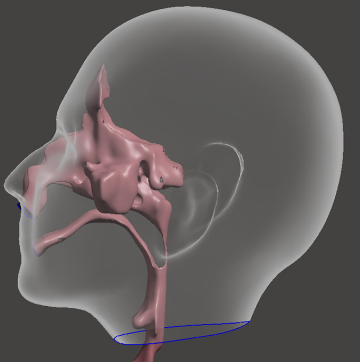

Fig 2. Three-dimensional reconstruction of the patient’s upper airway derived from MRI scans acquired in the supine position.

Following the MRI acquisition, the next step is to create a patient-specific 3D model of the upper airway lumen from the collected image stack. This process, known as segmentation, involves using specialized medical image processing software (like MIMICS or 3D Slicer) to manually or semi-automatically trace the boundary between the air column (the airway lumen) and the surrounding soft tissues (e.g., the tongue, soft palate, pharyngeal walls) on each 2D image slice. The excellent soft-tissue contrast from the MRI is crucial here for accurate boundary detection. Once all slices are segmented, the software then interpolates and stitches the 2D contours together to generate a continuous 3D surface model of the airway, typically exported as a triangulated surface file (like an STL or IGS). This 3D surface represents the computational domain – the internal volume where the air flow physics will be simulated – and its geometric accuracy directly determines the fidelity of the final CFD results for predicting sleep apnea-related airflow characteristics.

Fig 3. Schematic illustration showing the approximate location of the upper airway within the human head.